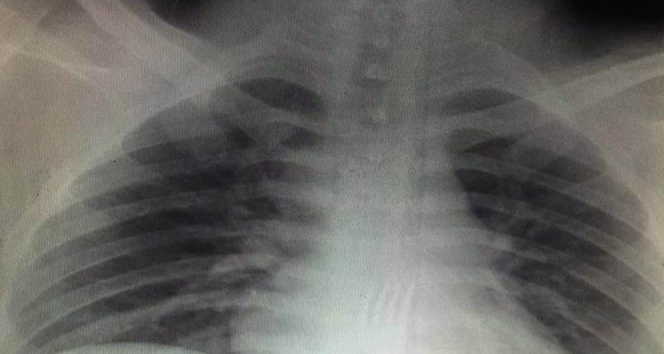

Konya’da yemek yediği sırada 15 santimetre boyundaki metal çatalı yutan 20 yaşındaki O.A., durumu fark eden ailesi tarafından Necmettin Erbakan Üniversitesi Meram Tıp Fakültesi Hastanesi Acil Servise götürüldü. Yapılan tetkikler sonucunda 20 yaşındaki gencin midesindeki çatalın yemek borusunun sonuna kadar inmiş olduğu belirlendi. Bunun üzerine ameliyata alınan O.A.'nın midesindeki çatal, Necmettin Erbakan Üniversitesi Meram Tıp Fakültesi Hastanesi Genel Cerrahi Anabilim Dalı Öğretim Üyesi Prof. Dr. Mehmet Erikoğlu tarafından gerçekleştirilen ameliyatın ardından çıkarıldı.

Ameliyatı gerçekleştiren Prof. Dr. Mehmet Erikoğlu, acil servise başvuran hastanın çatal yuttuğunun söylenmesi üzerine gerekli tetkikleri yaptıkların ve ardından hastayı hemen ameliyata aldıklarını söyledi. Erikoğlu, mideden küçük bir kesi ile 15 santimetre boyundaki çatalı bulunduğu yerden çıkardıklarını ifade etti.